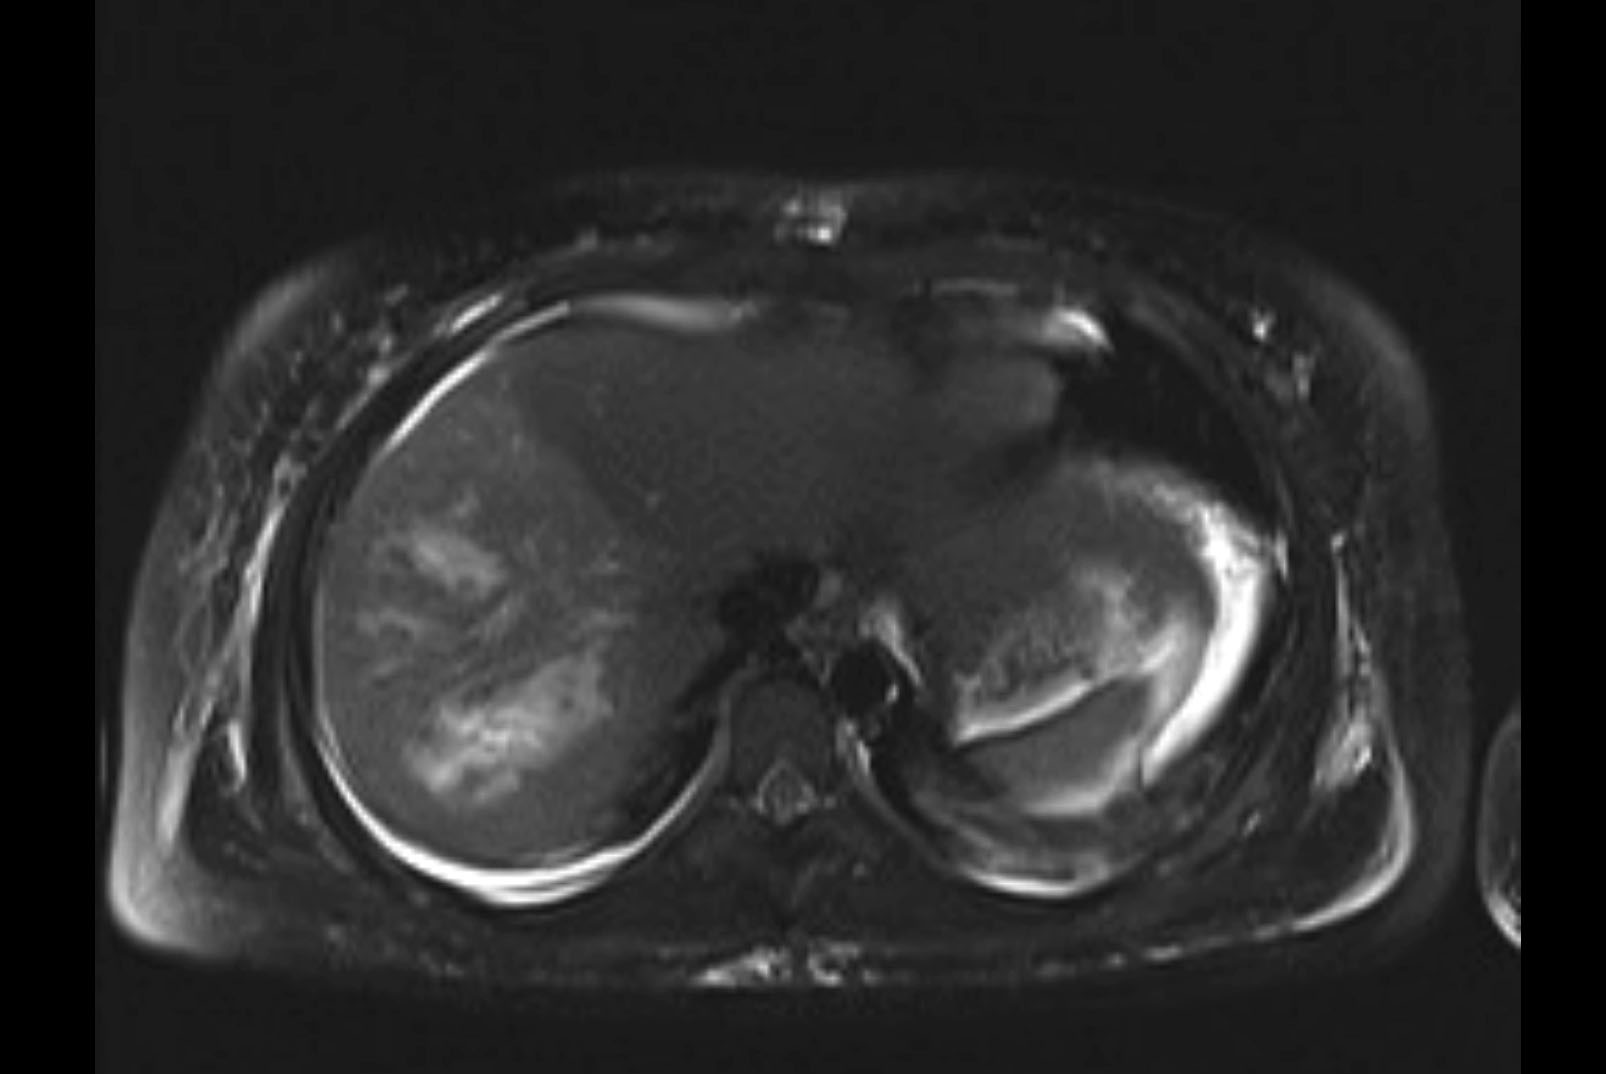

MRI T1